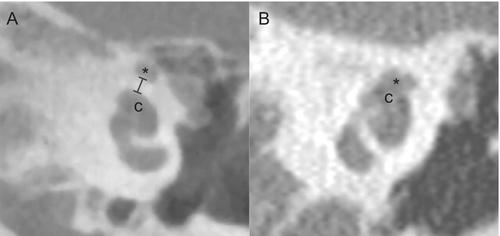

A retrospective review of 314 ears from 294 adult CI recipients was conducted. Two blinded reviewers measured CFPW and identified cases with CFD from the preoperative or postoperative high-resolution computed tomography (CT) scan. Analyses included the associations of CFPW and CFD with FNS, defined as facial movement elicited by CI stimulation. Audiologic and surgical data were reviewed for electrode characteristics and management of FNS.

Reviewers had excellent inter-rater reliability for CFPW measurements (intraclass correlation coefficient = 0.974). CFPWs were significantly smaller in ears with FNS (median: 0.40 mm) compared to those without FNS (median: 0.48 mm; p = 0.003). The prevalence of CFD was 3.2% (n = 10) and 70% of cases with CFD experienced FNS (relative risk [RR] = 14.2, 95% CI: 6.88–25.50, p < 0.001). Cases with CFD demonstrated a higher rate of FNS regardless of electrode type (lateral wall versus precurved).